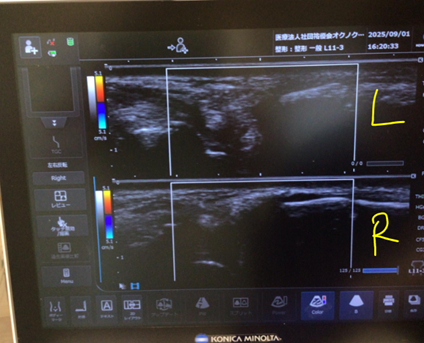

診察時のエコー検査では、左手首の小指側の膜に強い腫れがあり、炎症が起きていることが確認されました。 これまでMRIは撮影されていませんでしたが、当院での画像評価や身体所見から、炎症に伴って痛みの原因となる異常な血管(モヤモヤ血管)ができていると判断し、TFCC損傷のカテーテル治療を提案しました。